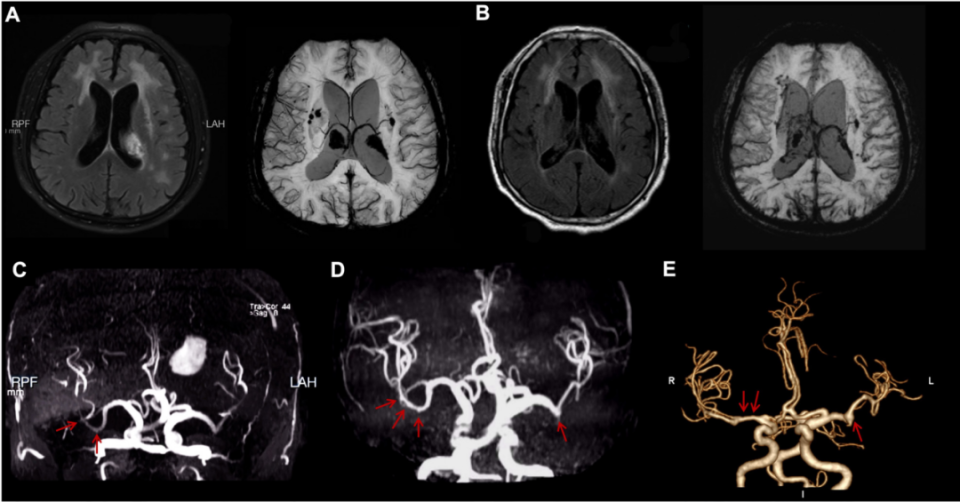

与此同时,该团队在2026年1月份《Stroke》(中科院一区,IF = 8.9)杂志上报道了一例罕见的神经布鲁氏菌病相关脑血管病变。该研究通过动态影像学证据,首次完整展示了由布鲁氏菌感染引发的脑白质损害、脑出血及大脑中动脉串珠样扩张,经过抗感染治疗后呈现出动态改变。

这一发现为感染相关脑血管病提供了全新的影像学表型,拓展了神经布鲁氏菌病的临床认知。齐鲁医院神经内科副研究员段若楠、医师高天宇为共同第一作者,赵玉英为通讯作者。